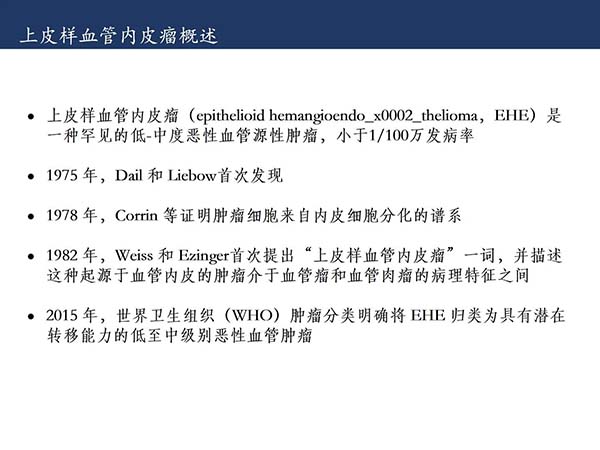

【杨柳科普】肺上皮样血管内皮瘤的影像表现